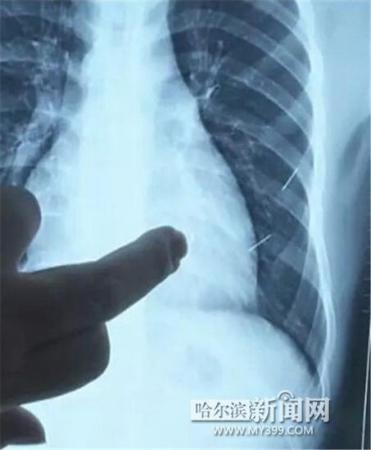

醫(yī)生指出X光片上的針狀物

昨日上午,記者在哈醫(yī)大二院第八住院部心外三病房找到了躺在病床上痛苦不堪的董立仁,家屬正在他身旁不斷安慰著他。見(jiàn)記者前來(lái),董立仁母親李百燕拿出一張X光片,上面可以清晰地看到胸腔內(nèi)一共有4根針狀物,其中一根在心臟部位,兩根在胸腔壁上,還有一根在腹腔壁上。

心外三病房董立仁的主治醫(yī)生告訴記者,董立仁送到醫(yī)院時(shí)病情很危險(xiǎn),隨時(shí)可能危及生命?!巴ㄟ^(guò)檢查發(fā)現(xiàn),他心臟內(nèi)有一個(gè)金屬異物,正好在心臟上。心臟每次跳動(dòng)都與其產(chǎn)生摩擦,導(dǎo)致出血,心包積液懷疑是血液。如果大量出血會(huì)凝結(jié)成血塊,血塊包裹住心臟就會(huì)影響心臟跳動(dòng),隨時(shí)都有停跳的危險(xiǎn)。心臟上的異物是致命傷,其余胸腔壁和腹腔壁的異物傷害不大。”

昨天16時(shí)30分左右取針手術(shù)開(kāi)始。因鋼針隨時(shí)會(huì)危及患者生命,此次手術(shù)定義為大型手術(shù)。開(kāi)胸后,醫(yī)生打開(kāi)董立仁心包,發(fā)現(xiàn)一枚鋼針已深深扎入心臟,僅露出1厘米長(zhǎng)度在外。拔出鋼針后,醫(yī)生發(fā)現(xiàn),這枚針長(zhǎng)達(dá)5厘米。受鋼針影響,心包出現(xiàn)大量積液,近800毫升。

隨后,在下胸壁位置,第二枚鋼針順利取出。在尋找另兩枚鋼針過(guò)程中,普外、胸外多名醫(yī)生也參與手術(shù),為主刀醫(yī)生提供更為穩(wěn)妥的處理建議。根據(jù)X光片顯示位置,醫(yī)生未在患者體內(nèi)找到剩余兩枚鋼針。醫(yī)生懷疑,其中一枚鋼針可能深藏在肋骨骨膜位置,無(wú)法尋找,最后決定結(jié)束手術(shù),做進(jìn)一步觀察,研究下一次手術(shù)方案。